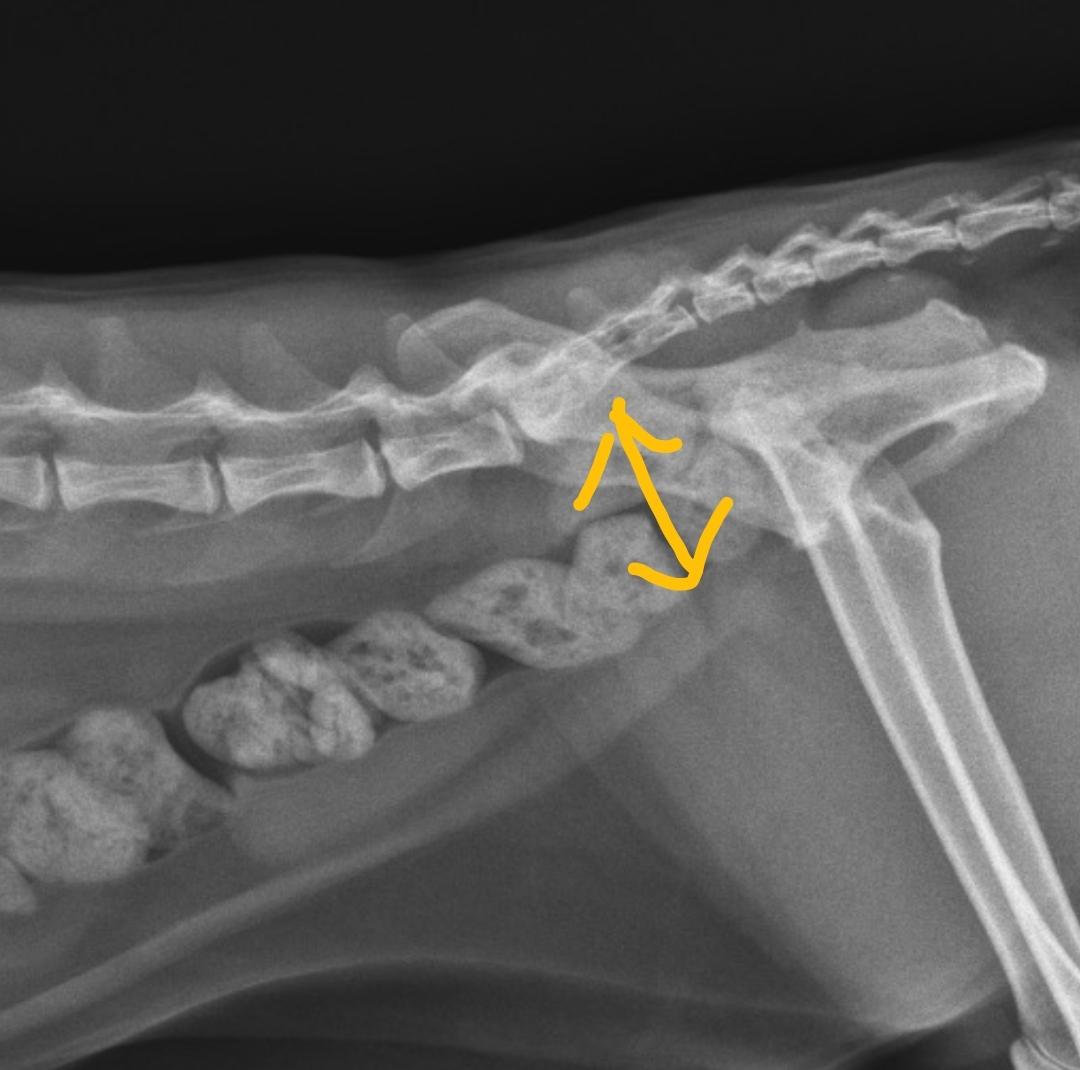

동물 병원에서 구토억제제만 처방받았고 이 엑스레이 보고서 가스찬거 말곤 별다른 증상 없다 하셨습니다. 다른선생님들도 같은 생각이신지 궁금하여 올려봅니다

거대 결장을 동반한 대장의 확장 수준이라 거대 결장과 관련한 기저 질환에 대한 평가가 필요한 수준이니 https://diamed.tistory.com/m/145 주치의와 상담 후 정밀 검사를 받으시는걸 추천합니다.